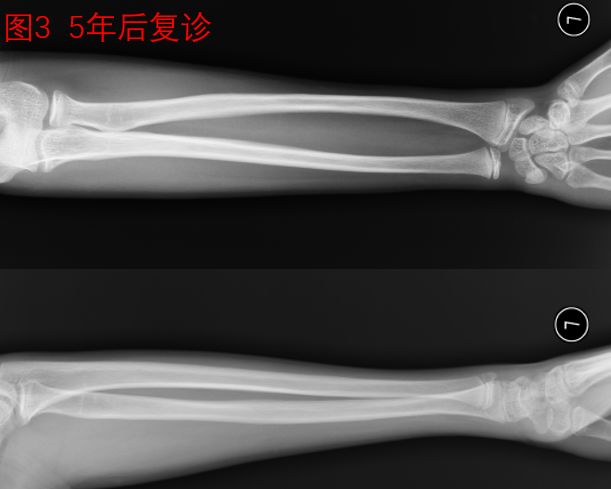

王××小朋友,在8岁运动时不慎摔伤导致前臂远端骨折,在当地医院经手法复位小夹板固定治疗。家长看了治疗后的片子,发现两根骨头断端都没有搭上,因此很难接受(图2)。去了多家医院咨询,有的医生建议开刀手术把骨头接上再用钢板钉住,家属心里又非常抗拒开刀手术,一时拿不定主意,后经同乡建议,10天后来我院就诊。我院骨科医生建议继续保守治疗,等待骨折塑形,家属采纳了建议。5年后再次复查X光片,骨折已经完全“长正”,看不到骨折的痕迹(图3)。